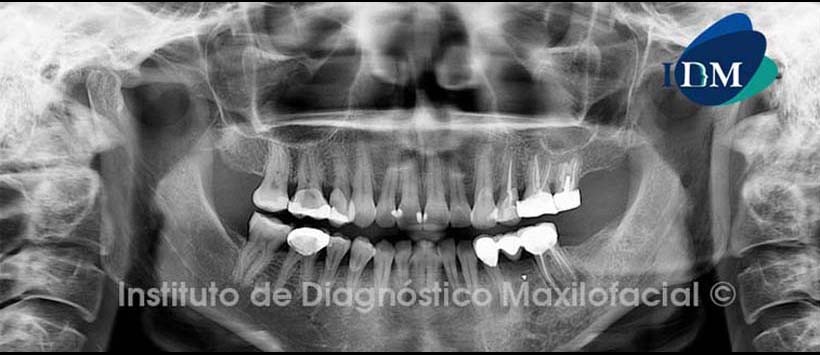

A la evaluación radiográfica panorámica (Fig.1) en zona de para sínfisis y cuerpo mandibular del lado izquierdo se observa aumento de la densidad ósea circundante, en zona apical de pieza dentaria 3.4 se evidencia proceso osteolítico, además en zona apical de pieza dentaria 3.6 se observa proceso apical, material de obturación en raíz distal con aparente bifurcación radicular.